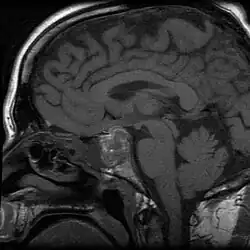

Apoplexy (from Ancient Greek ἀποπληξία (apoplexia) 'a striking away') refers to the rupture of an internal organ and the associated symptoms. Informally or metaphorically, the term apoplexy is associated with being furious, especially as "apoplectic". Historically, it described what is now known as a hemorrhagic stroke, typically involving a ruptured blood vessel in the brain; modern medicine typically specifies the anatomical location of the bleeding, such as cerebral apoplexy, ovarian apoplexy, or pituitary apoplexy.[1][2][3]

From the late 14th to the late 19th century, the diagnosis apoplexy referred to any sudden death that began with abrupt loss of consciousness, especially when the victim died within seconds after losing consciousness. The word apoplexy was sometimes used to refer to the symptom of sudden loss of consciousness immediately preceding death. Strokes, ruptured aortic aneurysms, and even heart attacks were referred to as apoplexy in the past, because before the advent of biomedical science, the ability to differentiate abnormal conditions and diseased states was limited. Although physiology, as a medical field, dates back at least to the time of Hippocrates, until the late 19th century, physicians often had inadequate or inaccurate understandings of many of the human body's normal functions and abnormal presentations. Hence, identifying a specific cause of a symptom or of death often proved difficult or impossible.[4][5][6][7][8]

To specify the site of bleeding, the term "apoplexy" is often accompanied by a descriptive adjective. For instance, bleeding within the pituitary gland is termed "pituitary apoplexy", and bleeding within the adrenal glands is referred to as "adrenal apoplexy".[9]

Apoplexy also includes hemorrhaging within the gland and accompanying neurological problems, such as confusion, headache, and impairment of consciousness.[10]